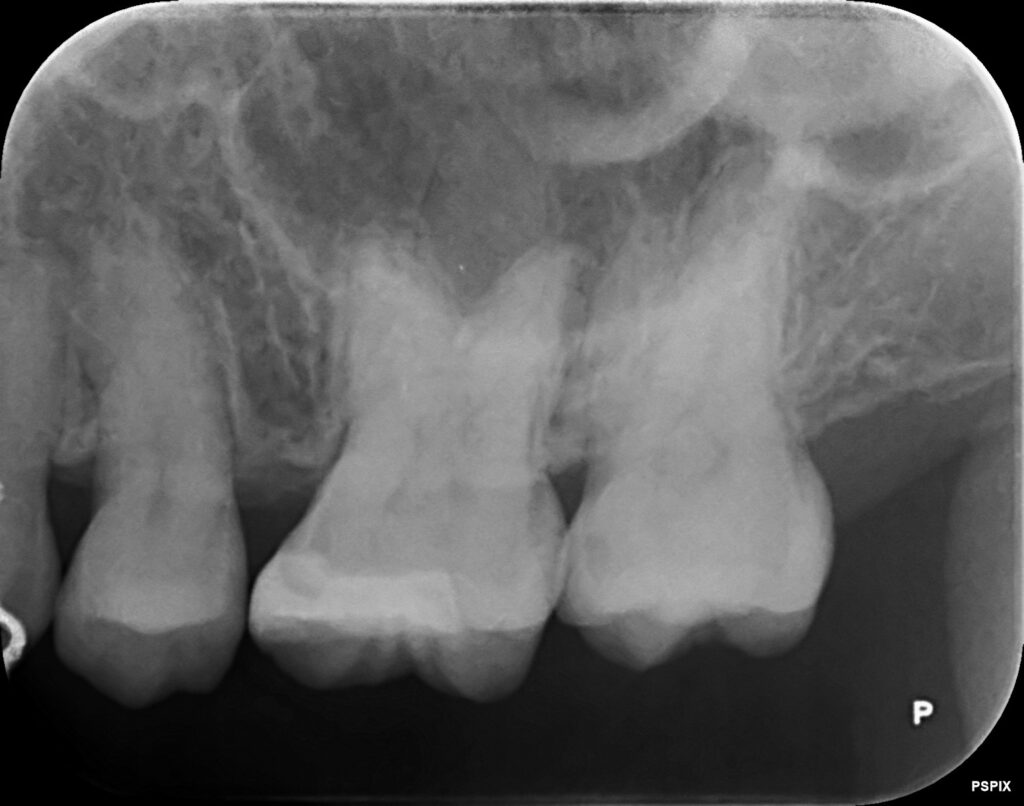

お口の中を見てみると、

左上の奥歯の2本です。

レントゲン写真を撮って歯の内部を検査してみます。

レントゲン写真を確認してみると、原因が分かりました。